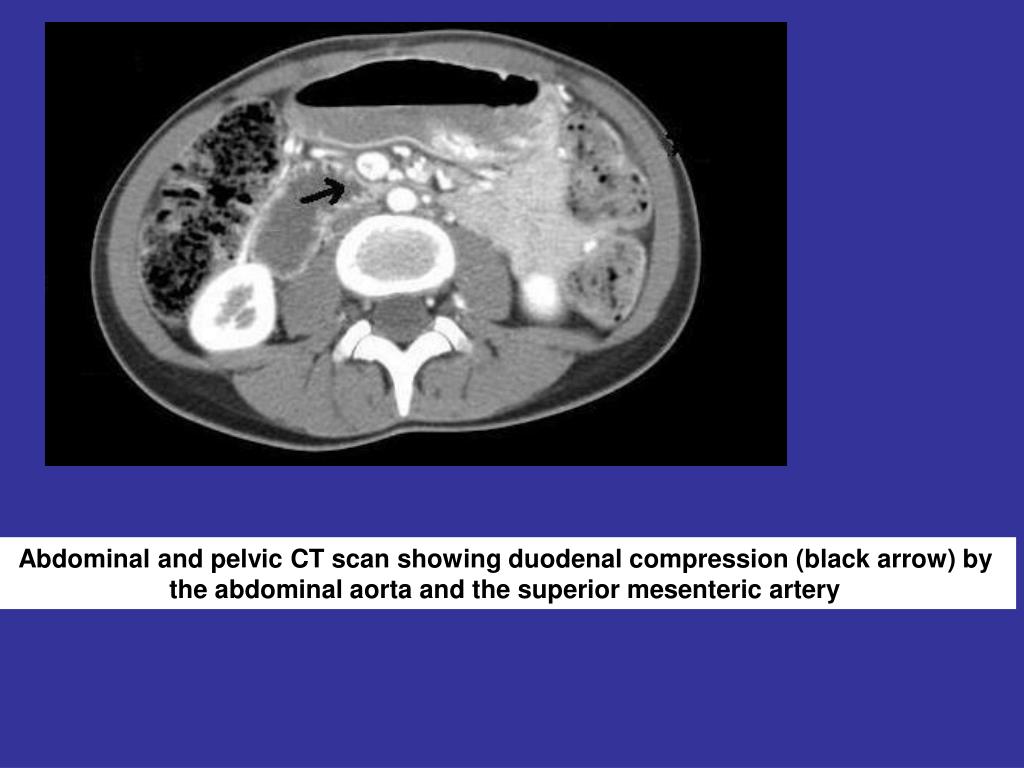

12. Abdominal and pelvic CT scan showing duodenal compression (black arrow) by the abdominal aorta and the superior mesenteric artery